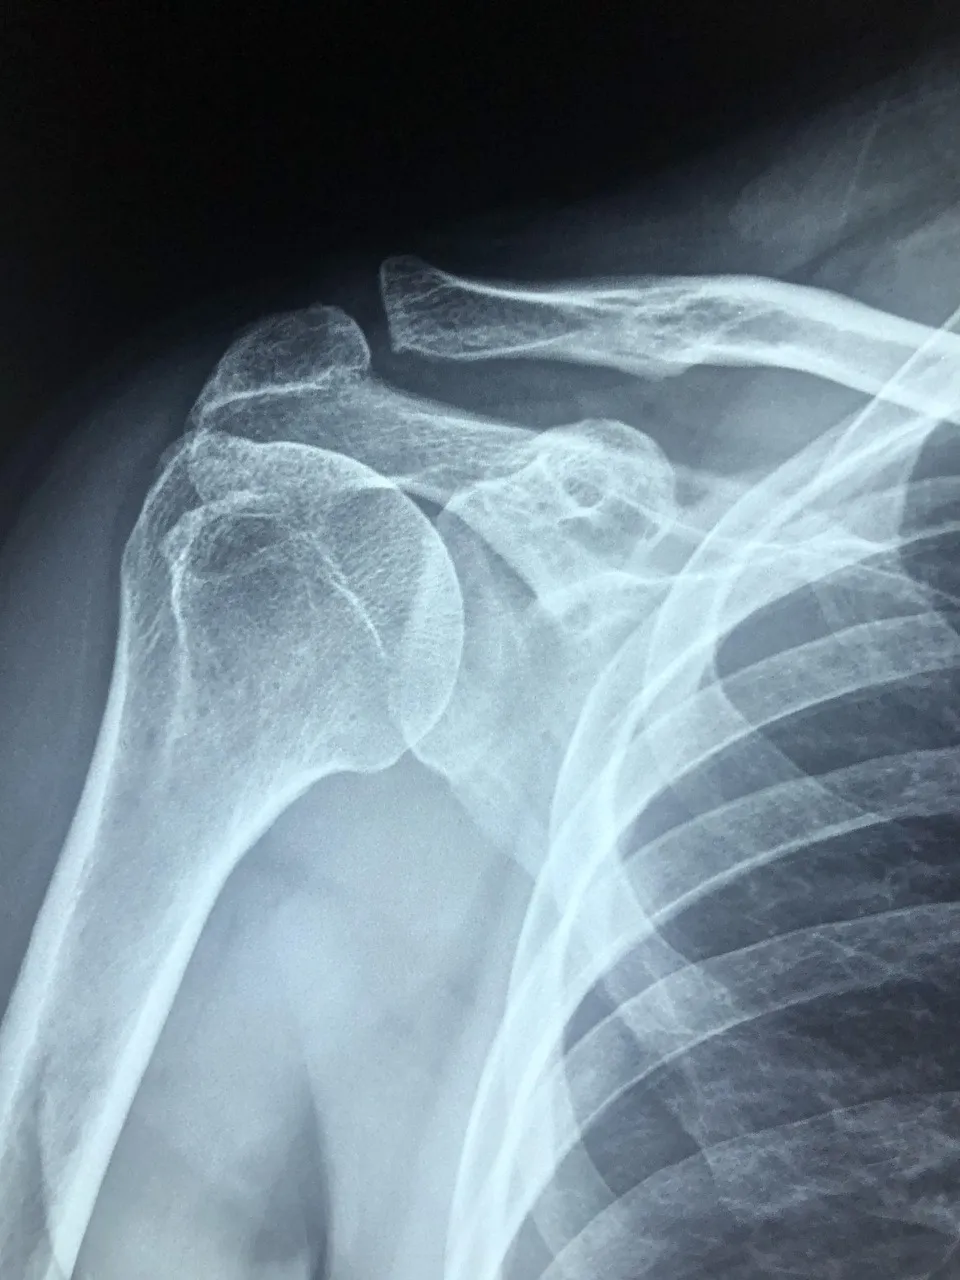

콘드로이친이란 무엇일까?

콘드로이친(Chondroitin)은 우리 몸의 연골과 결합조직 속에 자연적으로 존재하는 성분으로

관절 사이에서 충격을 흡수하고 마찰을 줄여주는 역할을 합니다.

나이가 들면서 콘드로이친이 점점 감소하면 관절이 뻣뻣해지고 통증이 생길 수 있다고 합니다.

콘드로이친 효능 2 – 연골 보호 및 재생 도움

콘드로이친은 단순히 통증을 완화하는 것에 그치지 않고,

-연골 세포의 손상을 줄이고 재생을 돕는 역할도 합니다.-